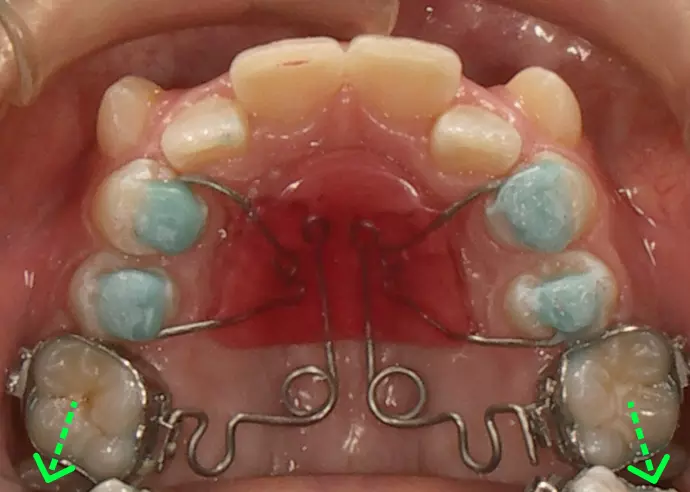

下の歯列を内側の装置で

広げ始めた